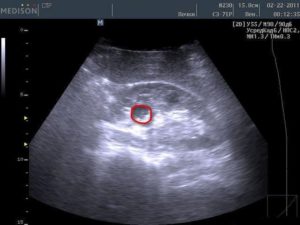

Из очаговых изменений чаще всего в почках выявляют кисты. Они выглядят как анэхогенные (полностью черные) структуры округлой формы с ровными отчетливыми контурами, дающие за собой усиление ультразвукового сигнала.

Может быть видно только одну кисту, но чаще их бывает несколько в одной или обеих почках. Как правило, никакой опасности простые кисты не представляют и встречаются у многих людей после 40 лет.

- Кистозные образования. Имеют вид анэхогенных (чёрных полностью) образований или пятен. Контуры у таких кист ровные, а форма округлая. При кистах сигнал ультразвука усиливается.